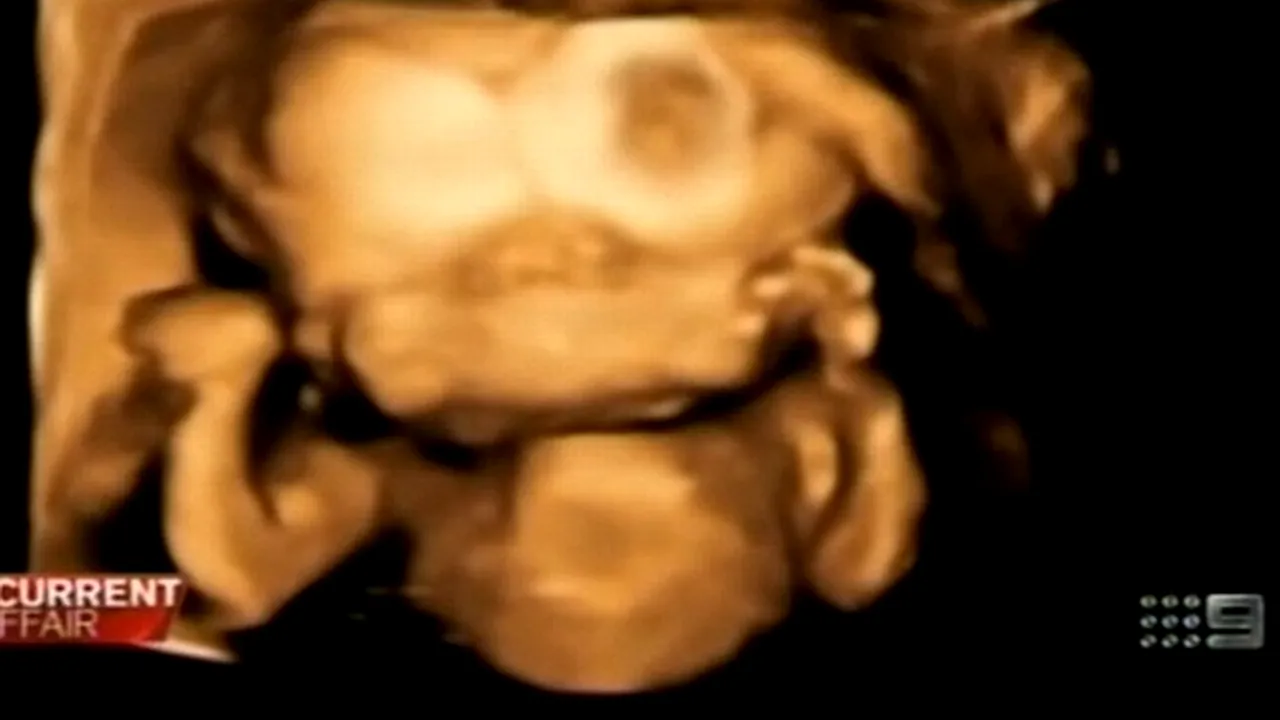

Doi viitori părinți din Australia au decis să nu întrerupă sarcina, deși au observat la ecografie că fiul lor are doi creieri și două fețe, iar medicii le-au recomandat să facă avort, scrie ninemsn.com.

Renee Young și Simon Howie credeau inițial că urma să aibă gemeni, însă o ecografie ulterioară a dovedit că, de fapt, fătul are două fețe și doi creieri conectați la același trunchi cerebral. În rest, fătul de 19 săptămâni are toate organele sănătoase.

Medicii au sfătuit-o pe Renee să facă avort, deoarece copilul va fi privit ca un ciudat și va avea o speranță de viață redusă.

Cu toate acestea, părinții au decis să-l păstreze. Renee și Simon trăiesc într-o suburbie a orașului Sydney, din ajutor social, și au decis să păstreze sarcina ”din motive morale”, deoarece consideră că un copil nu trebuie omorât dacă se dezvoltă normal.

Cel mai asemănător caz s-a petrecut în India, în urmă cu 6 ani, iar fetița respectivă a murit la 2 luni deoarece nu se putea hrăni corespunzător.